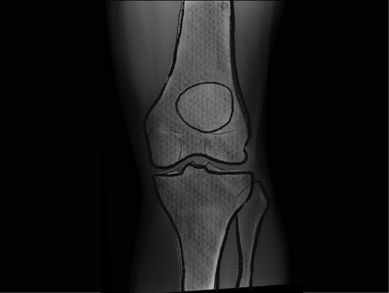

Total knee replacement

Experience the benefits of robotic knee replacement, offering accuracy and improved joint function for long-term relief.

Partial knee replacement

Targeted robotic surgery for partial knee replacement, preserving healthy tissue while relieving pain and restoring movement.